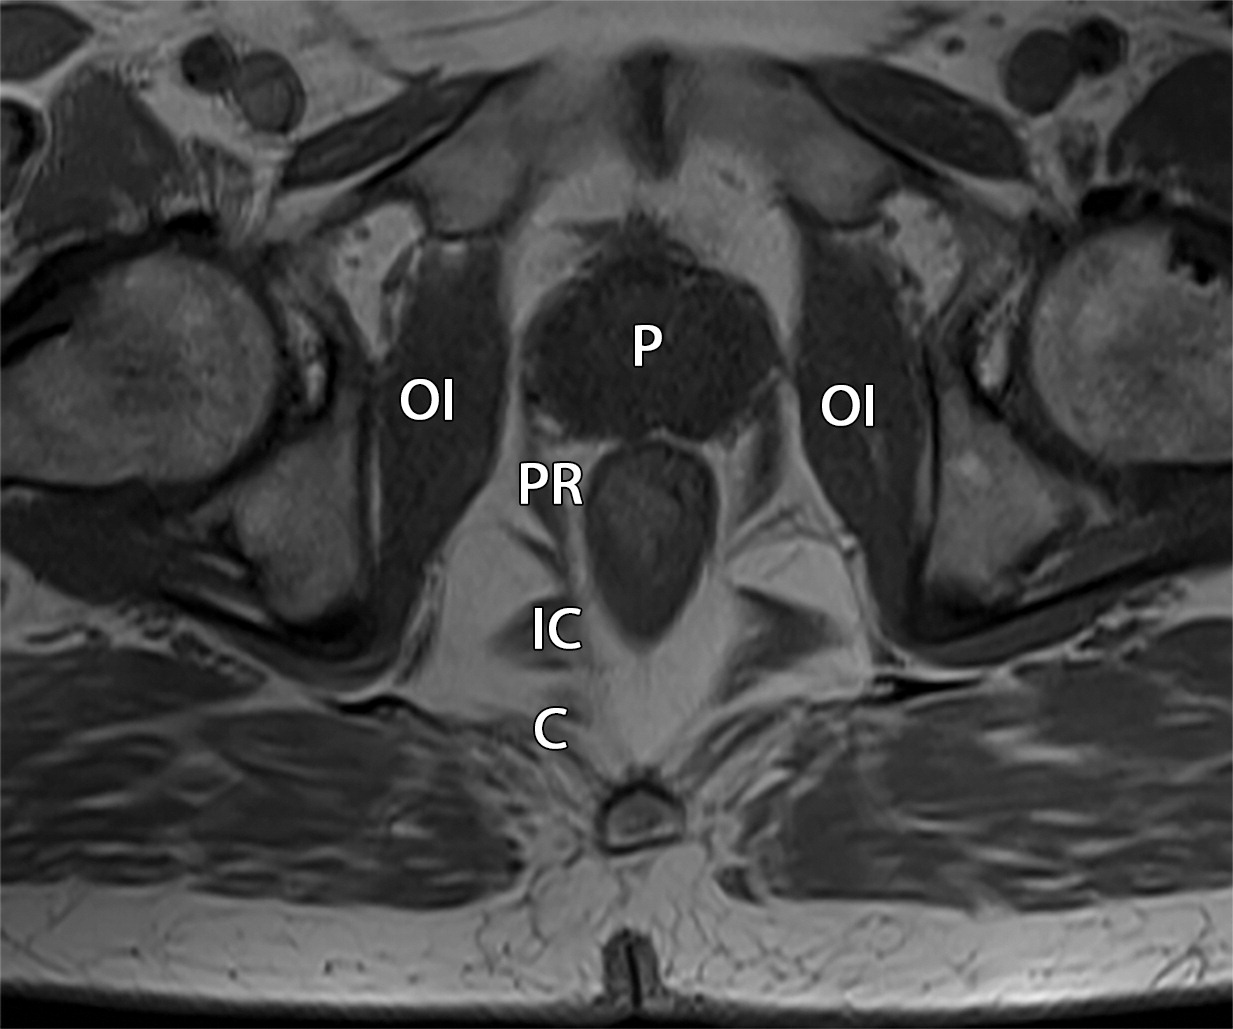

50岁以上男性骨盆和盆底的MRI解剖。

提肛肌(LA),由耻骨直肠肌(PR)、耻骨尾骨肌(PC)和髂尾骨肌(IC)组成;尾骨肌(C),前列腺(P),闭孔内肌(OI),会阴浅横肌(STP),球海绵体肌 (B), 坐骨海绵体肌(ISC),肛门外括约肌(EAS),肛门内括约肌(IAS),直肠(R),尿道括约肌(SU),也称为尿道外括约肌(U),它包围着整个膜性尿道。6774449af17bb1b8df6e83ab4e9fa158.jpeg